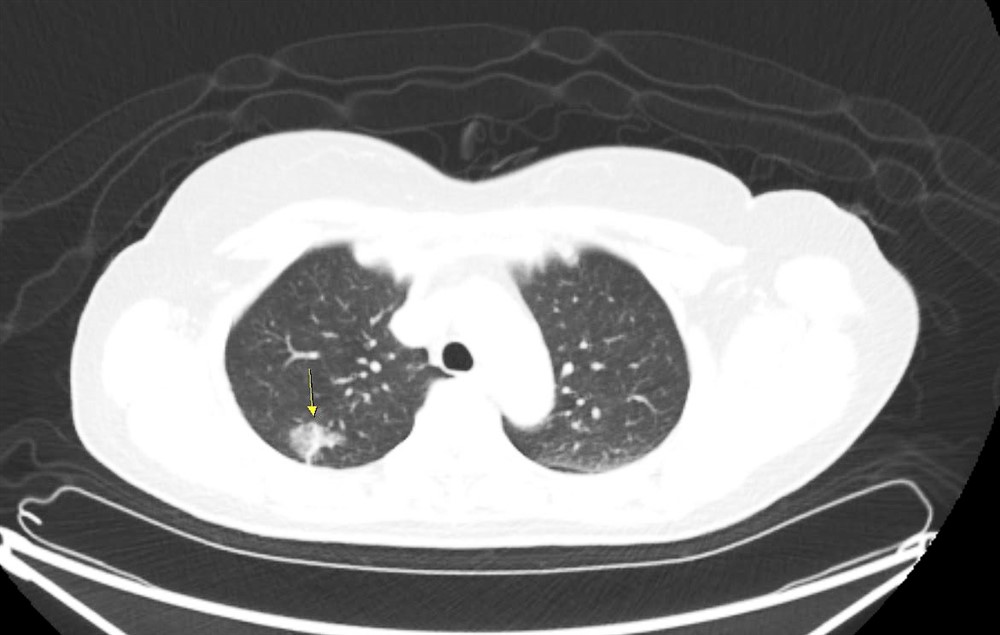

徐中平副院長說,目前肺癌病例近七成是肺腺癌,共同點是沒有明顯症狀。有些病灶的電腦斷層影像看起來像是毛玻璃的灰影(箭頭所指處),如果病灶小於一公分,且無實心變化,就可能是癌前病變或原位癌。圖/徐中平提供

肺癌病人早期幾乎沒症狀,而腫瘤只要達一公分就可能轉移,若已出現咳嗽、咳血、喘、疼痛、體重減輕等症狀時,多已經到晚期。徐中平副院長指出,經低劑量電腦斷層檢查發現如毛玻璃霧面狀病灶,就需要定期追蹤。若腫瘤超過零點八公分或質地較扎實,則病灶有可能轉成惡性。如情況許可,手術切除為第一選擇,其他尚有放射線治療、化學治療、標靶治療、免疫治療等各種療法。其中標靶治療與免疫治療須先做基因檢測,有特定基因表現才適用,而健保對符合條件的病人也會給付。